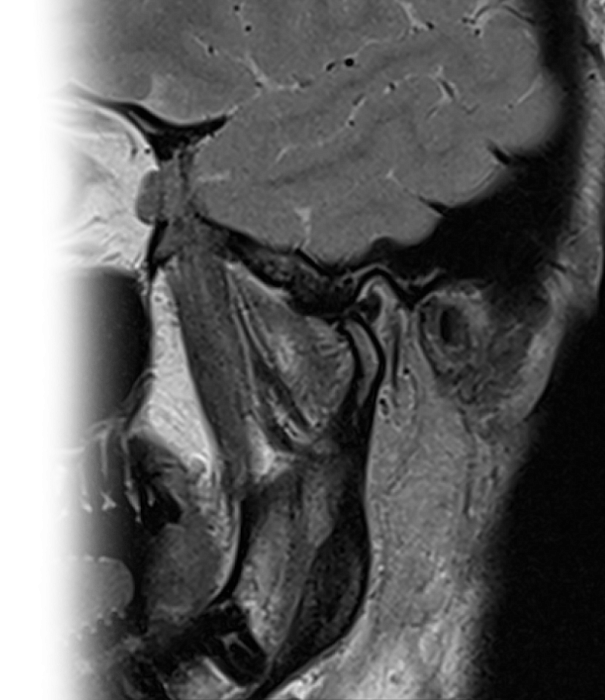

МРТ височно-нижнечелюстных суставов

Магнитно-резонансная томография височно-нижнечелюстных суставов – важный метод исследования, который позволяет оценить состояние височно-нижнечелюстных суставов (ВНЧС).